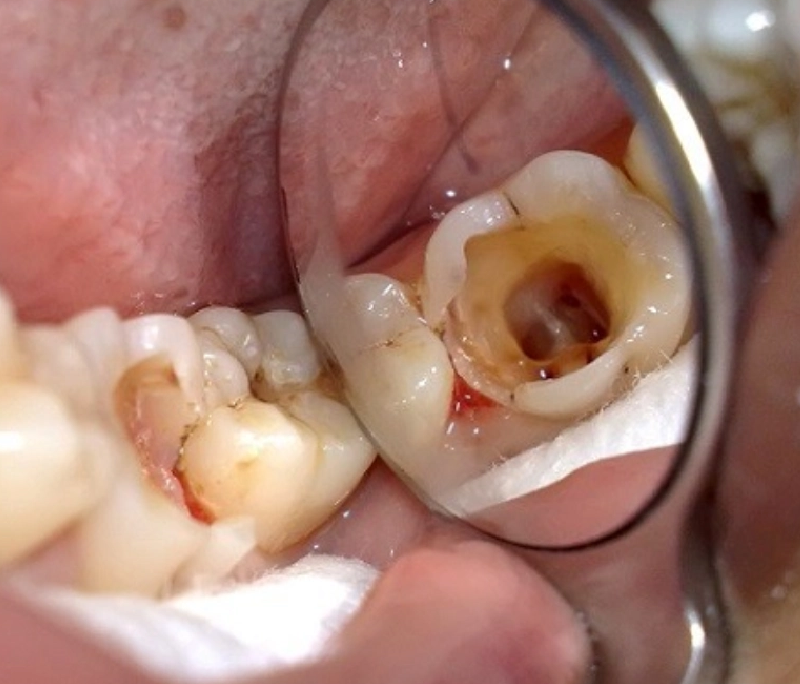

Đau răng dữ dội? Răng ê buốt kéo dài khi ăn đồ nóng lạnh? Đó có thể là những dấu hiệu cảnh báo tủy răng của ...